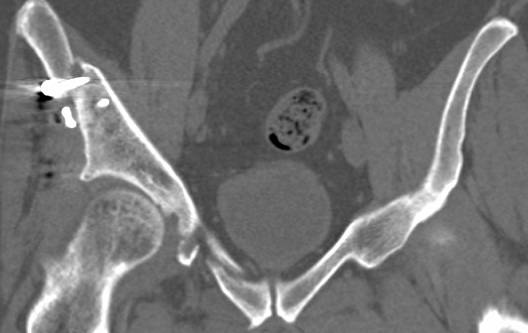

[Ortho] перелом правой половины таза

высылаю дополнительно  сканы.